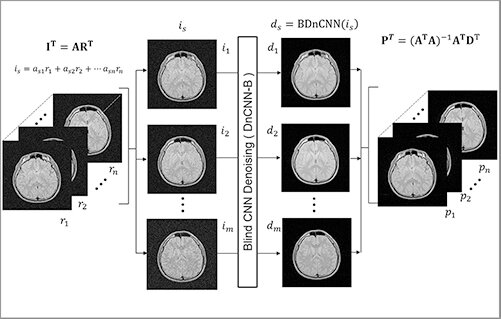

深層学習を利用した雑音除去法は、従来の非線形フィルタを大幅に上回る特性を示し、大きな注目を集めている。宇都宮大学学術院 伊藤聡志教授は、本研究において、MRI画像を対象とし、3つの観点から性能改善を図った。第1に活性化関数に従来のReLUではなくSwishを応用したこと、第2に雑音量が未知であり、かつ、空間可変な雑音画像に適応しうるブラインド雑音除去を導入したことである。第3に隣接する画像を線形加算して複数の加算画像を作成し、加算画像に対しブラインド雑音除去を行い、その後に連立方程式を解く並列型雑音除去法の導入である。実験の結果、Swishの採用によりReLUを上回るPSNRが得られた。また、並列型雑音除去法の採用により画質劣化を抑制した雑音除去を行えることが示された。

雑音除去性能を改善するために、これまで利用されていないSwishを活性化関数に使用した。17層をもつ深層学習ネットワークを使用し、さまざまな雑音量をもつ画像をランダムに学習させる方法により雑音量が未知な場合であっても雑音量に応じて適切に雑音除去を行うブラインド雑音除去の性能を与えた。提案法の有効性を高めるために複数の雑音画像に重みを変えつつ線形加算した複数の画像を作成し、それらに雑音除去を行う並列型雑音処理法(ParBID)を提案した。重み付き加算により雑音の分布が異なるので、元は同じ画像群であっても異なる雑音除去を受けることになる。雑音除去後に重み付き加算の逆演算を行うので加算により生じた画像の"ぼけ"の影響を受けない雑音除去像を得ることができる。